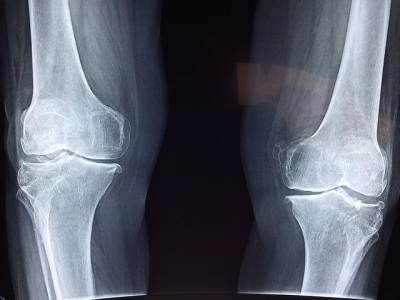

1. MSM의 효능 관절건강

MSM의 유황성분은 우리몸의 면역체계에 영향을 미쳐 세포 활동을 촉진시키는 방식으로 항염증제 역할을 합니다. 관절염, 건염, 요통, 근육경련에 효과가 좋다고 합니다.

MSM은 단백질 구조를 형성하여 뼈, 근육을 구성하는데 기여하며 관절 부종이나 경직을 일으키는 염증 반응을 낮추는데도 도움이 되어 관절의 통증을 줄여주는데 도움을 줍니다.

5. MSM의 효능 연골 건강

MSM은 연골건강에도 도움을 줍니다. 관절의 콜라겐 생성을 돕고 관절 사이의 연골 파괴를 제한하는 역할을 해서 연골 건강 보완에 도움을 줍니다.